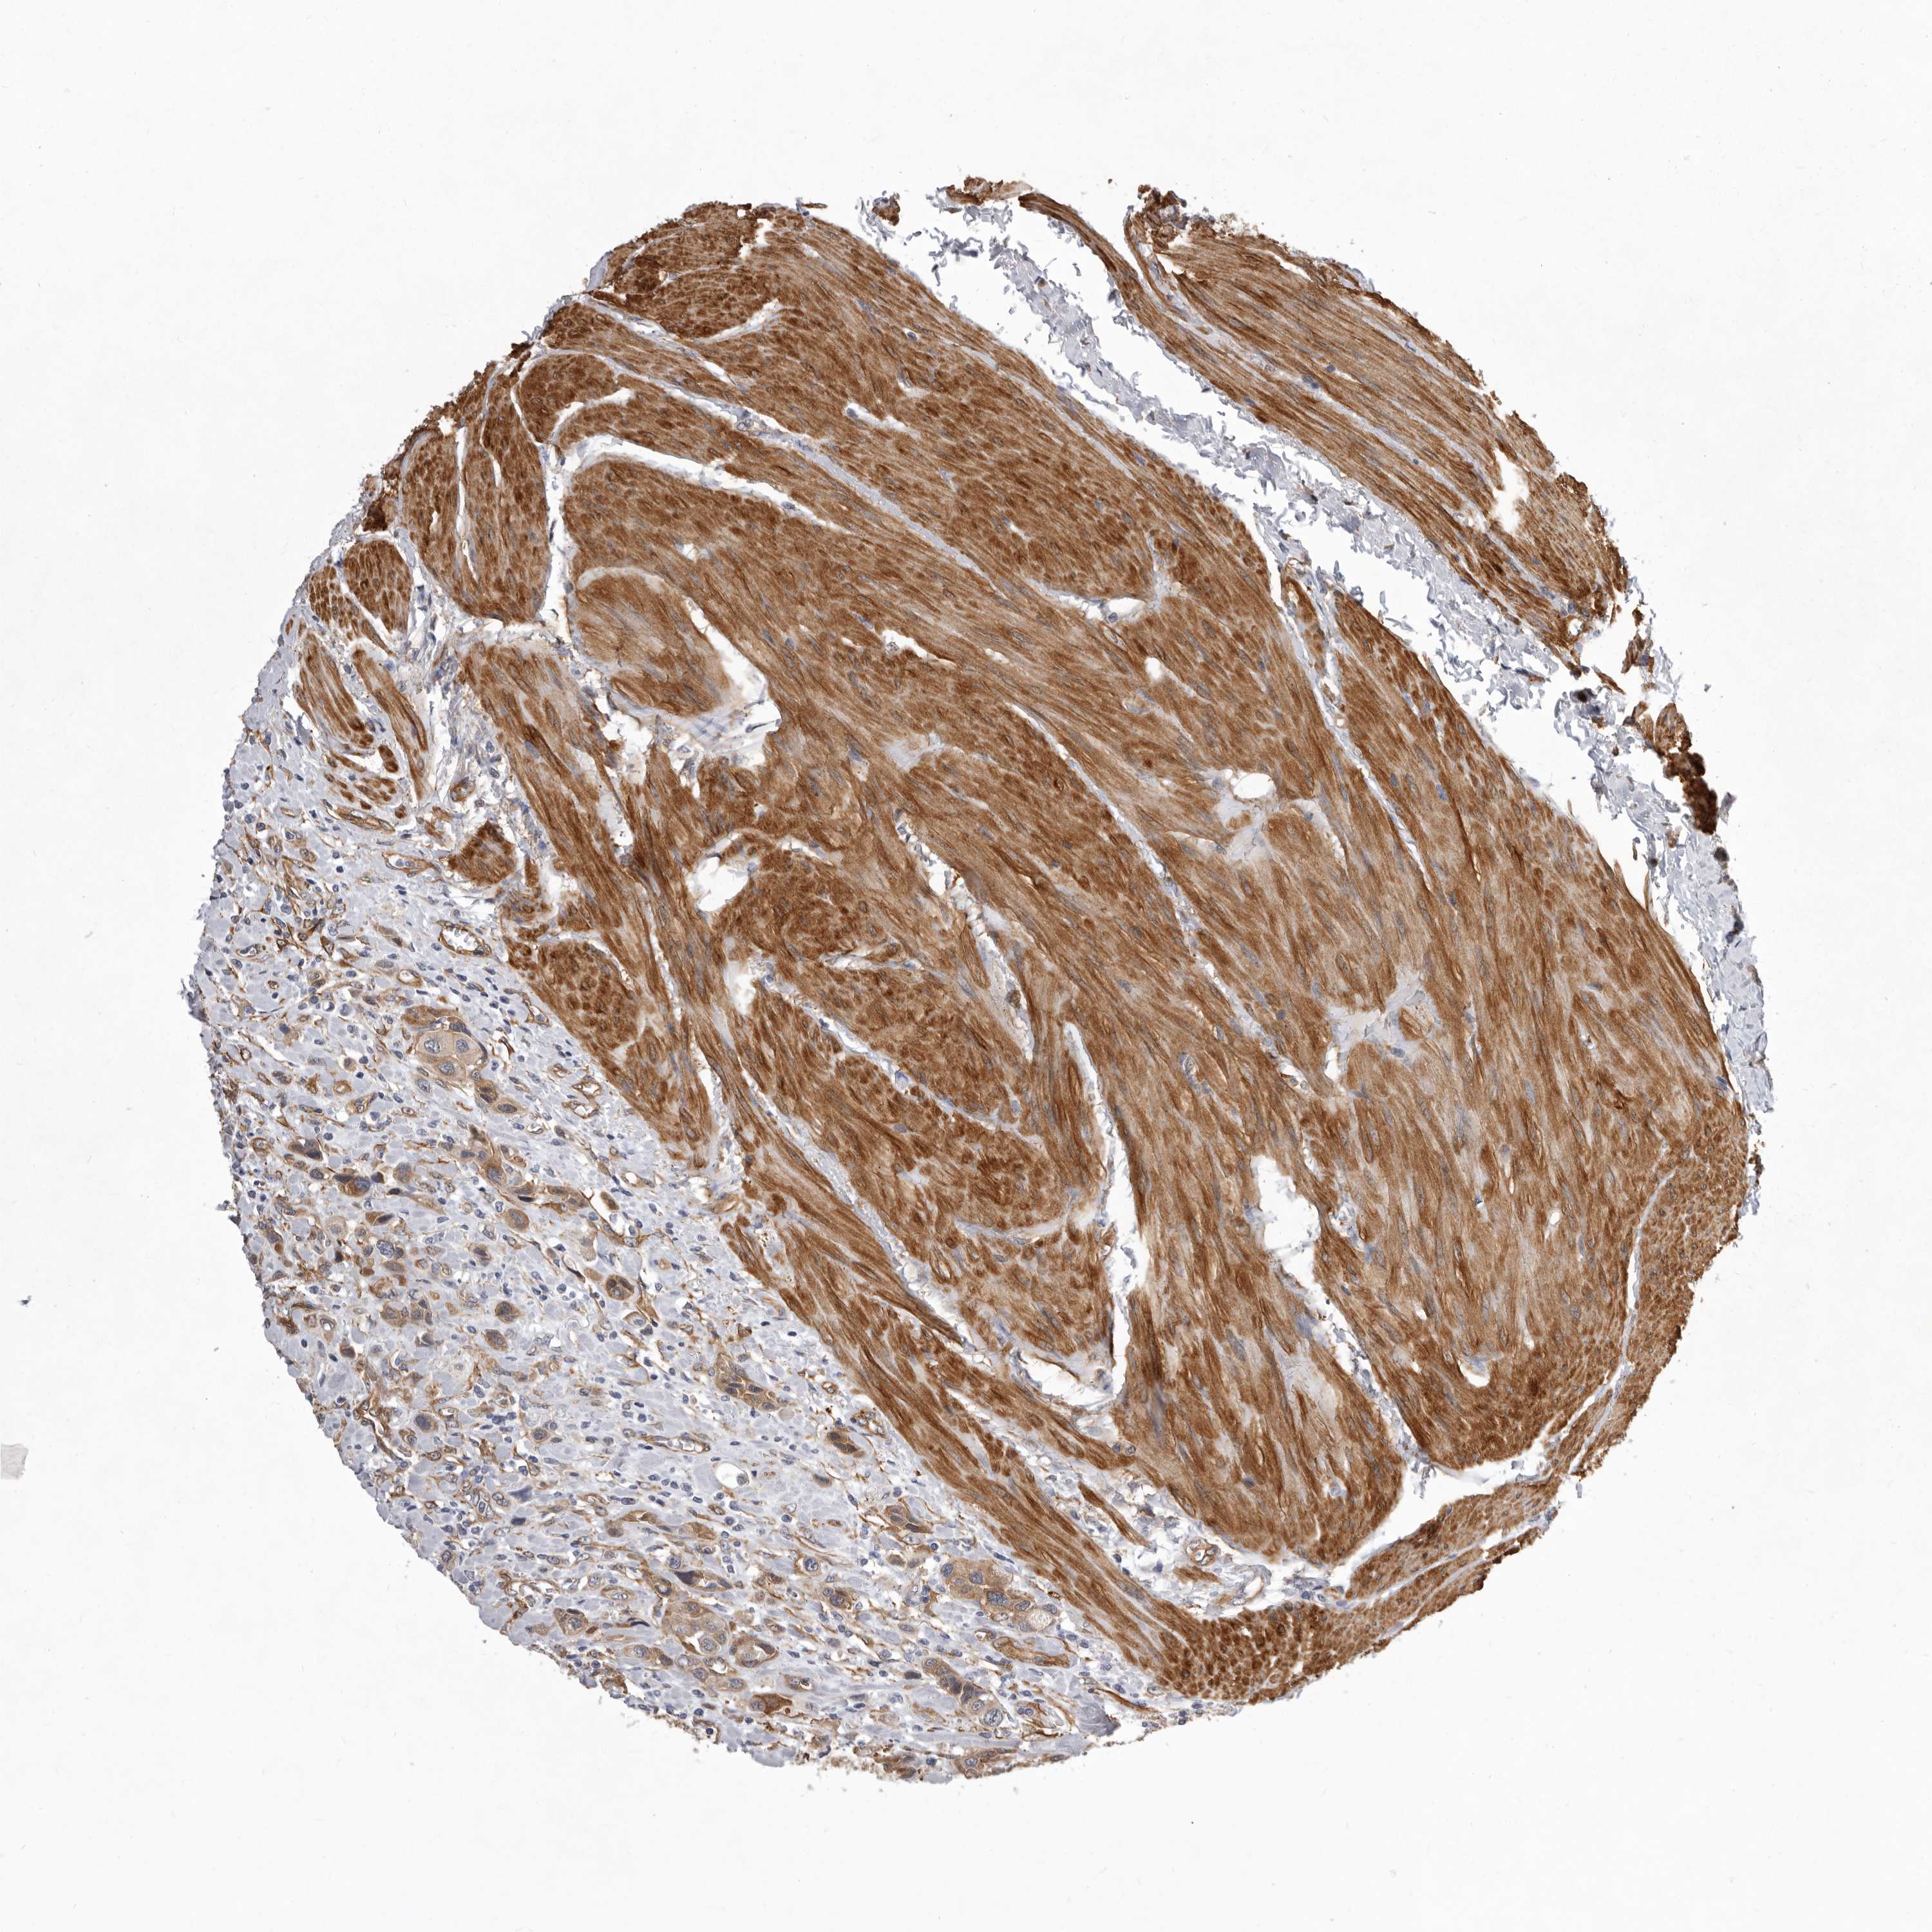

UROTHELIAL CANCER - Protein expressioni

A mouse-over function shows sample information and annotation data. Click on an image to view it in a full screen mode. Samples can be filtered based on level of antibody staining by selecting one or several of the following categories: high, medium, low and not detected. The assay and annotation is described here.

Note that samples used for immunohistochemistry by the Human Protein Atlas do not correspond to samples in the TCGA dataset.

Antibody stainingi

Antibody staining in the annotated cell types in the current human tissue is reported as not detected, low, medium, or high, based on conventional immunohistochemistry profiling in selected tissues. This score is based on the combination of the staining intensity and fraction of stained cells.

Each image is clickable and will lead to virtual microscopy that enables deeper exploration of all samples and also displays staining intensity scores, fraction scores and subcellular localization as well as patient and tissue information for each sample.

Antibody HPA028448

Antibody HPA028696

Urothelial carcinoma, Low grade

Urothelial carcinoma, High grade